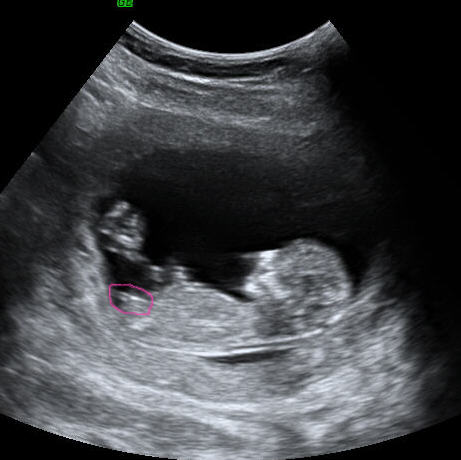

12 weeks . Between 8 - 12 weeks of pregnancy is a good time for a dating scan . A 2-D image of a baby at about 8-9 weeks . Small arms are becoming visible, sticking out slightly in the middle of the baby . The wavy line near the bottom of the image measures the heartbeat which in this baby is 188 beats per minute .